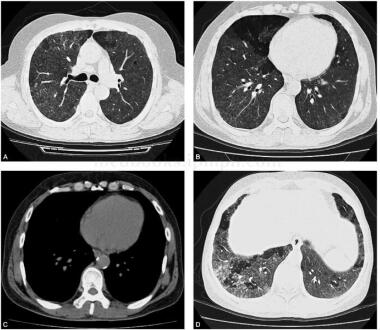

患者女,56岁,以间质性肺疾病入院。当地医院胸片示双肺多发斑片影,考虑肺炎,给予多种抗生素治疗无效,后怀疑间质性肺炎而服用泼尼松,治疗效果不佳。既往史:工作中接触铅粉2年。查体:双下肺可闻及少许爆裂音,杵状指趾(-)。胸部高分辨率CT(HRCT)双肺野透光度减低,可见散在弥漫的毛玻璃密度影,局部地图样改变;部分病灶融合成片,有支气管充气征,部分病灶呈网状蜂窝状,双侧弥漫性小叶间隔增厚,怀疑过敏性肺泡炎或肺泡蛋白沉积症,支气管肺泡灌洗(bronchoalveolar lavage,BAL)涂片过碘酸雪夫染色(PAS染色)阳性,经多次纤支镜分段支气管肺泡灌洗后,症状明显改善,出院后定期随诊(图1)。

图1 肺窗内两肺见弥漫分布的斑片状毛玻璃密度影,延伸至胸膜下;肺窗内双肺内毛玻璃密度影局部呈地图样分布,分界清楚;相同层面的纵隔窗,未见明显异常,毛玻璃密度影未见显示;右肺下叶病灶内见斑片样高密度影,密度稍高于毛玻璃密度